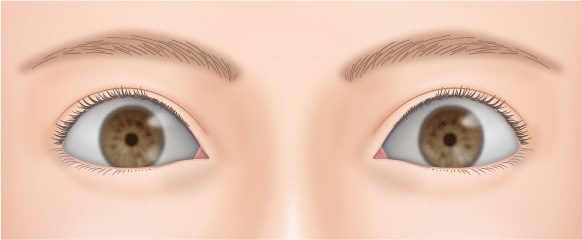

二重の幅が広くなり過ぎて、いかにも整形っぽい目になることがあります。

無理に幅広の二重を作った場合、腫れが半年以上も続き、ハム目のようになる場合があります。